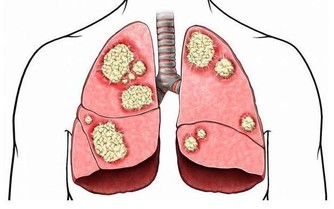

乾燥綜合徵患者的特點是陰津虧虛為本,燥熱火氣為標,從而表現為兩目、口腔、皮膚等的燥熱津傷之象。因此,多食養陰生津類食品可改善乾燥症狀,如百合、山藥、梨、蘆根等。

中醫治療疾病,都講究辨證分型,風濕病也有很多分型,藥食同源,從飲食防治原則上來說,可以將風濕病籠統地劃分為寒熱兩型。